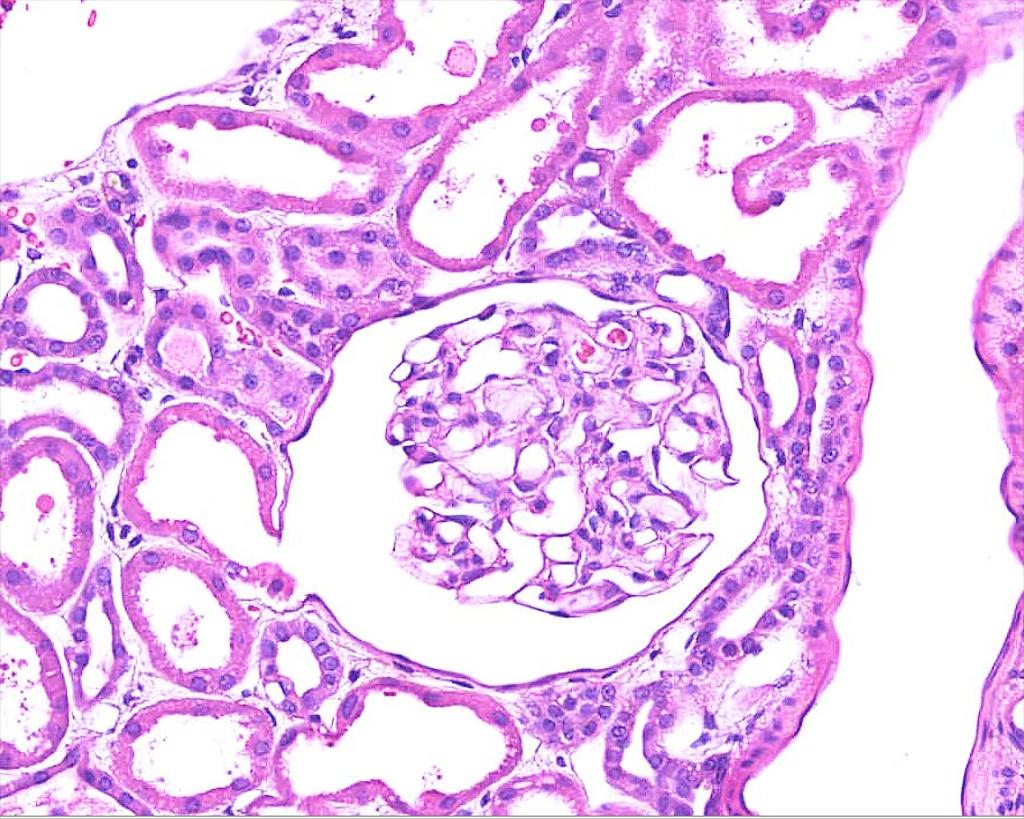

Normal